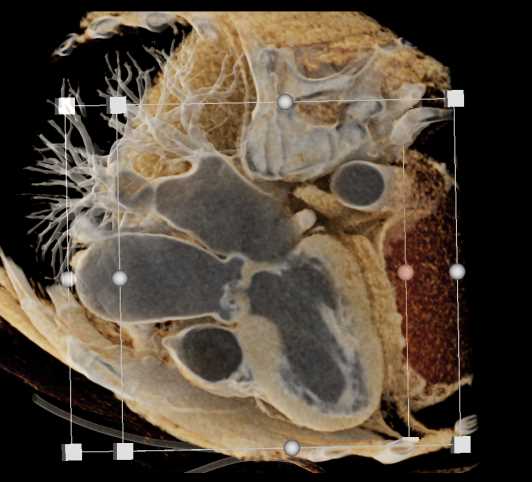

Primary Spindle Cell Carcinoma of the Right Ventricle